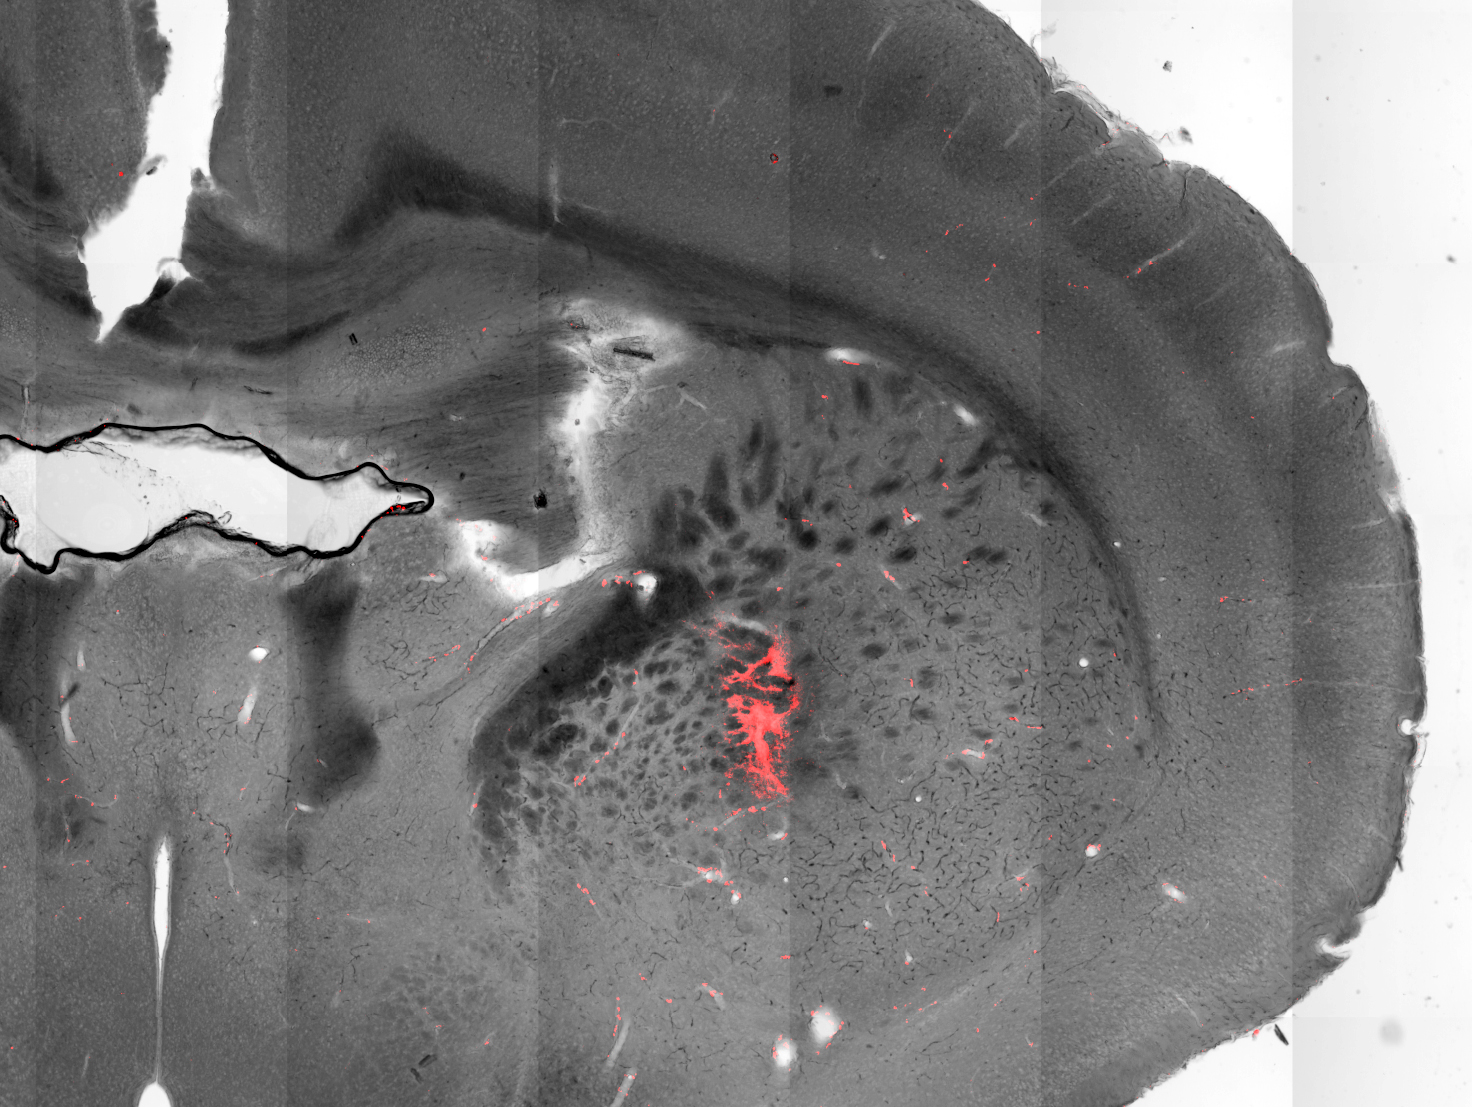

Scientists have used magnetic nanoparticles to stimulate neurons deep in the brain to evoke body movements of mice. This image shows a section of a mouse brain with injected magnetic nanoparticles (colored red) covering targeted cells in the striatum. Credit: Munshi et al, eLife

Stimulating cells in the motor cortex caused the animals to run, while stimulating cells in the striatum caused the animals to turn around. When the scientists activated a deeper region of the brain, the mice froze, unable to move their extremities.